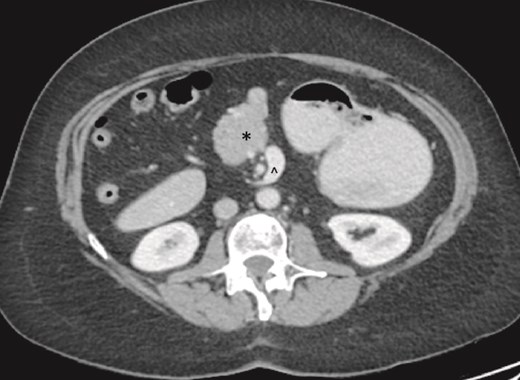

On examination, the abdomen was soft but mildly distended. Bowel sounds were heard, and the epigastrium was mildly tender. Standard bloodwork was normal. Review of an abdominal computerized tomography (CT) scan from 4 years prior showed congenital malrotation of the bowel, with the small bowel to the left of the midline and colon entirely to the right (Fig. 1). There was partial agenesis of the dorsal pancreas (Fig. 2), azygous continuation of the inferior vena cava (IVC), a retroaortic and retrocrural left renal vein, and an unremarkable spleen alongside some splenules. The PV traversed anterior to the first part of the duodenum (Fig. 3). There was relative narrowing of the distal stomach and the duodenum was nondilated.

Preduodenal PV seen crossing the duodenum (D) causing partial obstruction.

A PDPV needs special consideration during duodenal and biliary tract surgery as there is an increased risk for ligation, tearing, division, and thrombosis due to excessive handling [1]. This is especially important during emergent laparotomy where cross-sectional imaging may not be performed prior to surgery. In our case, a CT scan was beneficial as the PDPV was readily visible traversing anterior to the duodenum and identifiable as a potential cause of duodenal obstruction. This was further confirmed during EGD when there was difficulty passing the gastroscope into the first part of the duodenum. This approach is similar to previous case reports where CT imaging and an EGD were performed prior to surgery [11, 12].